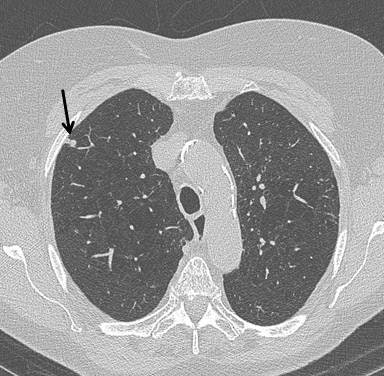

CT detects many benign nodules and masses (about 25 for every cancer detected), they continued. In the National Lung Screening Trial (NLST), 59/26,722 (0.2%) of participants underwent a CT-guided lung biopsy for a benign lesion and seven (0.03%) had a major complication. Clinical management pathways were not prespecified in the NLST, and where data were available, 2.2% of participants underwent PET, thus receiving a much higher radiation dose. The Dutch-Belgian NELSON trial and the UKLS pilot trial both employ low-dose CT follow-up by using volume measurements rather than diameter to detect growth, and this reduces the number of false-positive screens and defines more accurately the need for invasive procedures.